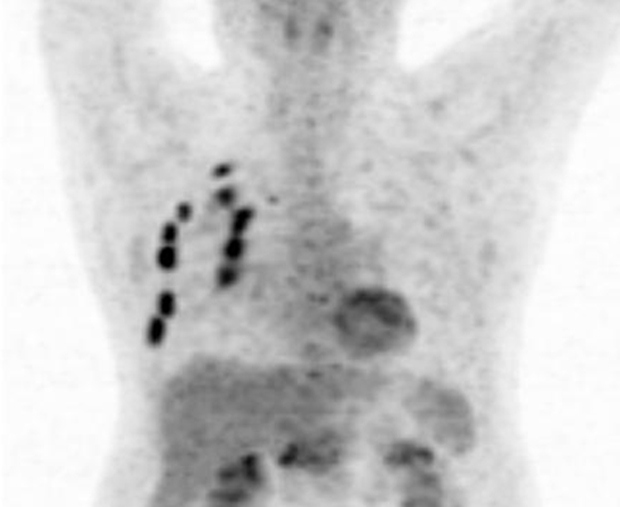

Puede existir actividad médula ósea reaccional a tratamientos estimulantes de colonias granulocíticas, post quimioterapia y/o por anemias severas (fig.3).